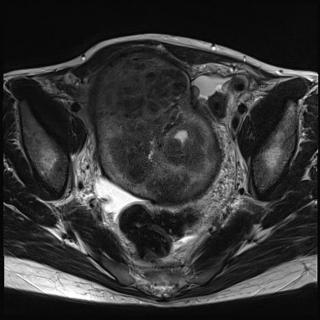

(Слева) Липоматозная гемангиоперицитома. При нативной КТ в аксиальной плоскости в нижних отделах малого таза определяется очень крупное образование, изоденсное по сравнению с мышцами и содержащее участки жировой плотности.

(Справа) У этого же пациента при МРТ в аксиальной плоскости на Т1ВИ выявленное в малом тазу образование содержит участки с сигнальными характеристиками жировой ткани и зоны, изоинтенсивные по сравнению с мышцами. Наличие жировой ткани и сложная структура образования чаще свидетельствуют в пользу липосаркомы, а не редко встречающейся липоматозной гемангиоперицитомы. (Слева) У этою же пациента при МРТ в аксиальной плоскости на Т2 ВИ в режиме FS выявленное в малом тазу образование характеризуется гетерогенным гиперинтенсивным сигналом и наличием гипоинтенсивных зон, соответствующих жировой ткани. Мочевой пузырь а придавлен опухолью к передней стенке малого таза.